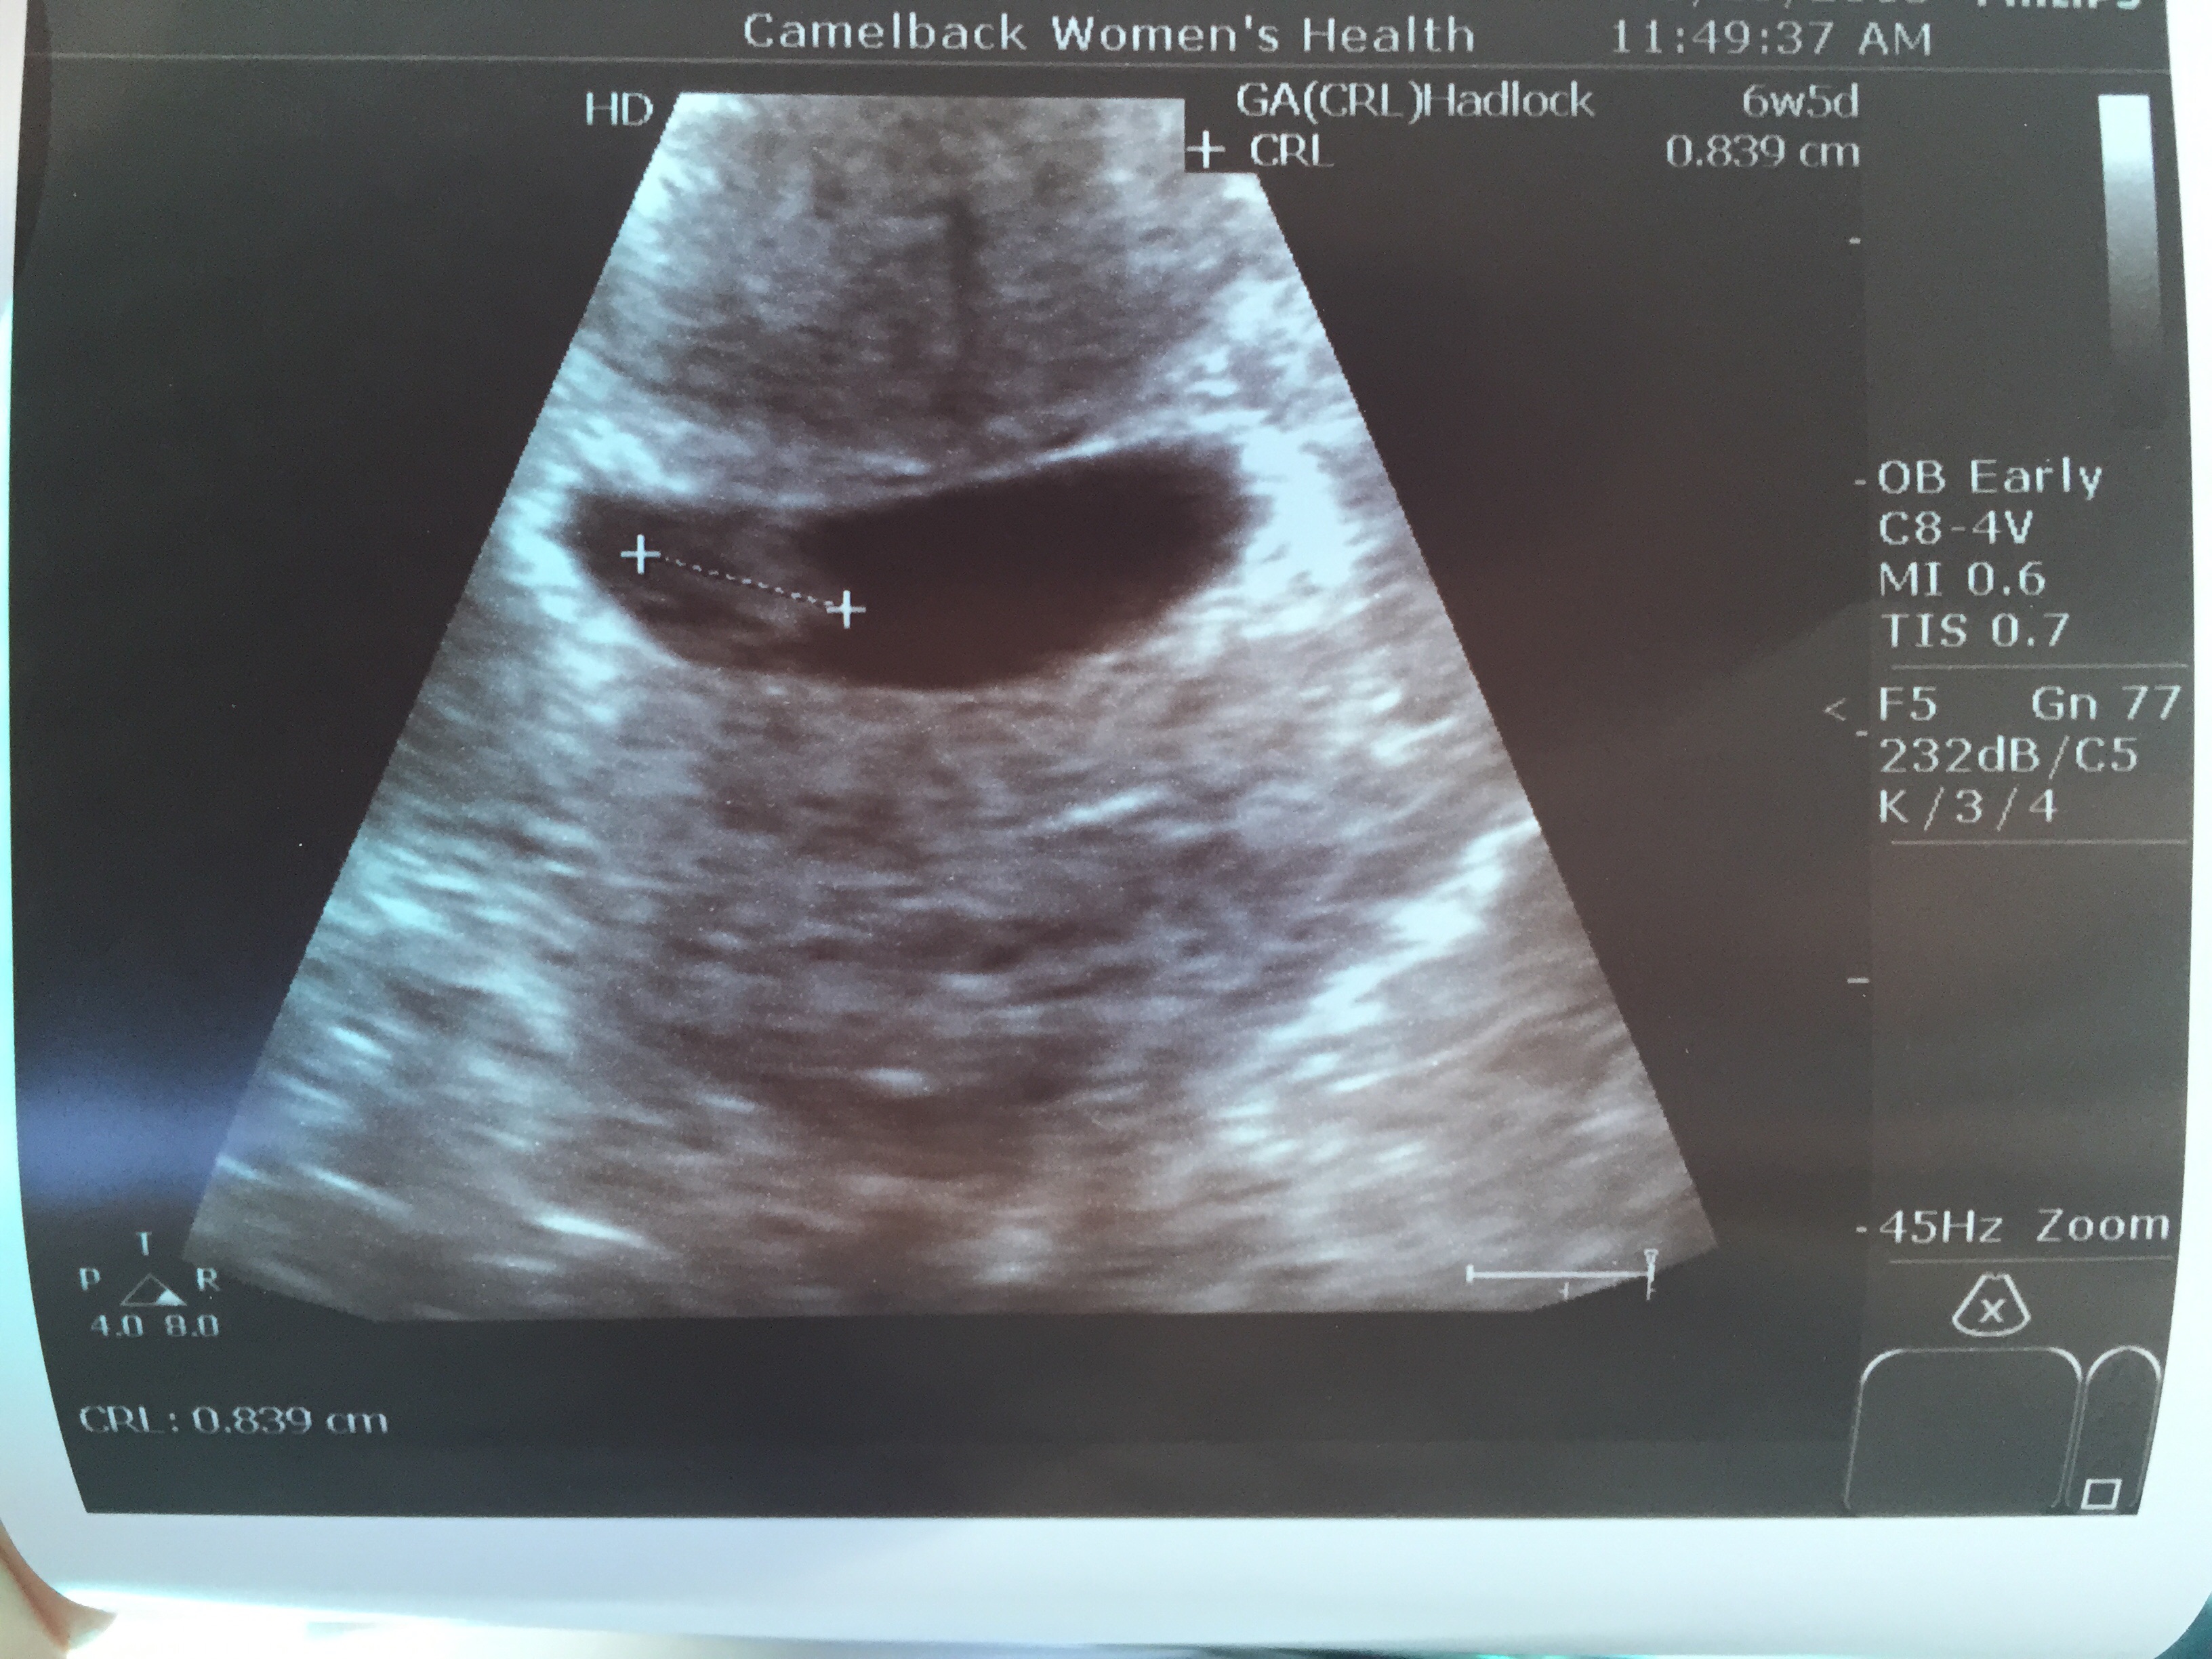

Today I get to add mine too!! 1 week less than estimated according to size. Good strong heartbeat. All looking good. 0.788cm at 6w 5days according to monitor.